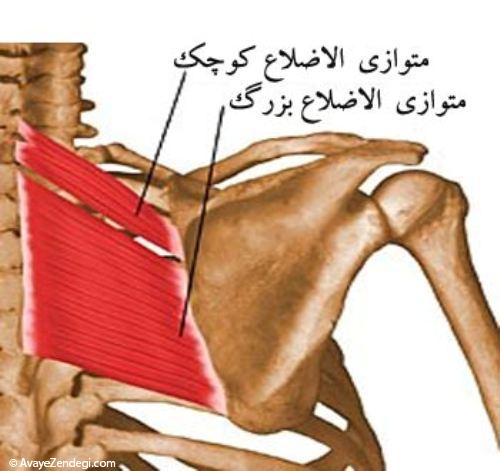

عضله متوازی الاضلاع

این عضله در اصل دو عضله است که شباهت زیادی در نحوه قرار گیری و عمل دارند. عضله متوازی الاضلاع بزرگ از روی خارهای مهره های دوم تا پنجم پشتی شروع می شود و به بخش تحتانی لبه داخلی استخوان کتف متصل می شود. جهت کشیدگی تارهای این عضله مایل است. عضله متوازی الاضلاع کوچک نیز از روی انتهای تحتانی رباط نوکه در پشت گردن و خارهای مهره های هفتم گردن و اول پشتی شروع شده و به ریشه خار استخوان کتف متصل می شود، تارهای این دو عضله به موازات هم قرار دارند.